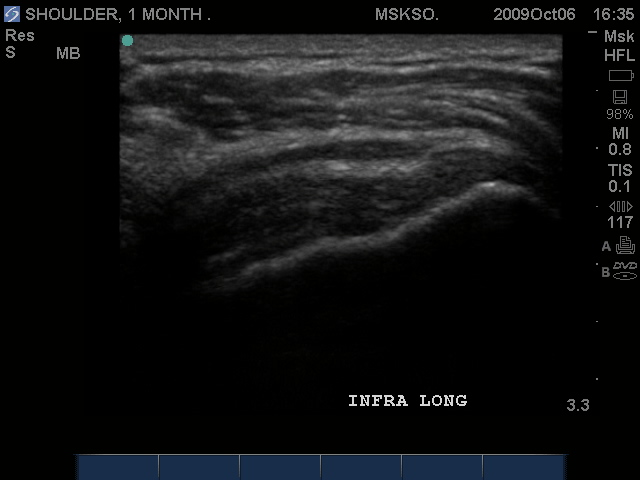

Long axis image of the Infraspinatus tendon over the posterior Greater Tuberosity also confirms bursal enlargement.